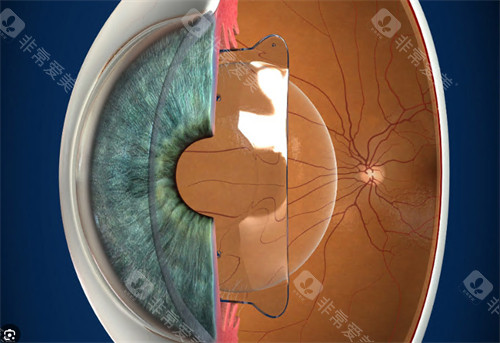

人工晶体依赖周边囊袋固定,若术中囊袋撕裂、术后剧烈运动或眼部受到外力撞击,晶体可能发生偏移或脱位。

患者会出现视力模糊、重影,甚至完全丧失视力。一位高度近视患者术后因搬运重物导致晶体脱位,需紧急手术重新固定晶体。

人工晶体度数需根据术前角膜曲率、眼轴长度等参数计算,但个体差异可能导致计算偏差。

对比敏感度下降:视觉细节的“模糊滤镜”

人工晶体无法完全模拟自然晶状体的调节功能,患者术后可能感觉视觉对比度降低,尤其在暗光环境下难以分辨物体细节。

手术决策需综合考量眼部条件、全身健康状况及个人需求。对于高度近视患者,若角膜厚度不足无法接受激光手术,ICL晶体植入仍是优选;对于白内障患者,人工晶体置换是改善视力的仅有途径。